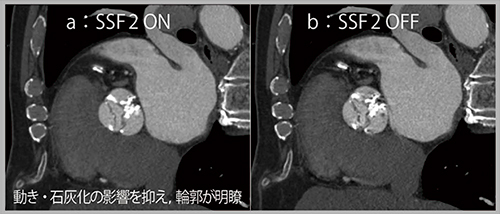

症例1は,超音波にて明らかな弁の開放制限を認め,二尖弁は左冠尖と無冠尖が癒合しているように見える(fused bicuspid)。CTでは,通常の4D画像にて二尖弁の癒合を確認できるが,アーチファクトの影響で時折描出が不鮮明となる(図1 b)。一方,SnapShot Freeze 2を適用すると,動きや石灰化の影響が抑制されて薄い弁尖の輪郭が明瞭となり,fused bicuspidであると確実に診断できる(図1 a)。また,TAVI術前評価にて左室流出路(LVOT)の面積を計測する際,通常のCTと比べてSnapShot Freeze 2を適用した画像ではLVOTの輪郭が明瞭であり,計測値に影響を与えるレベルの補正効果を得られた。

図1 症例1:大動脈弁狭窄症